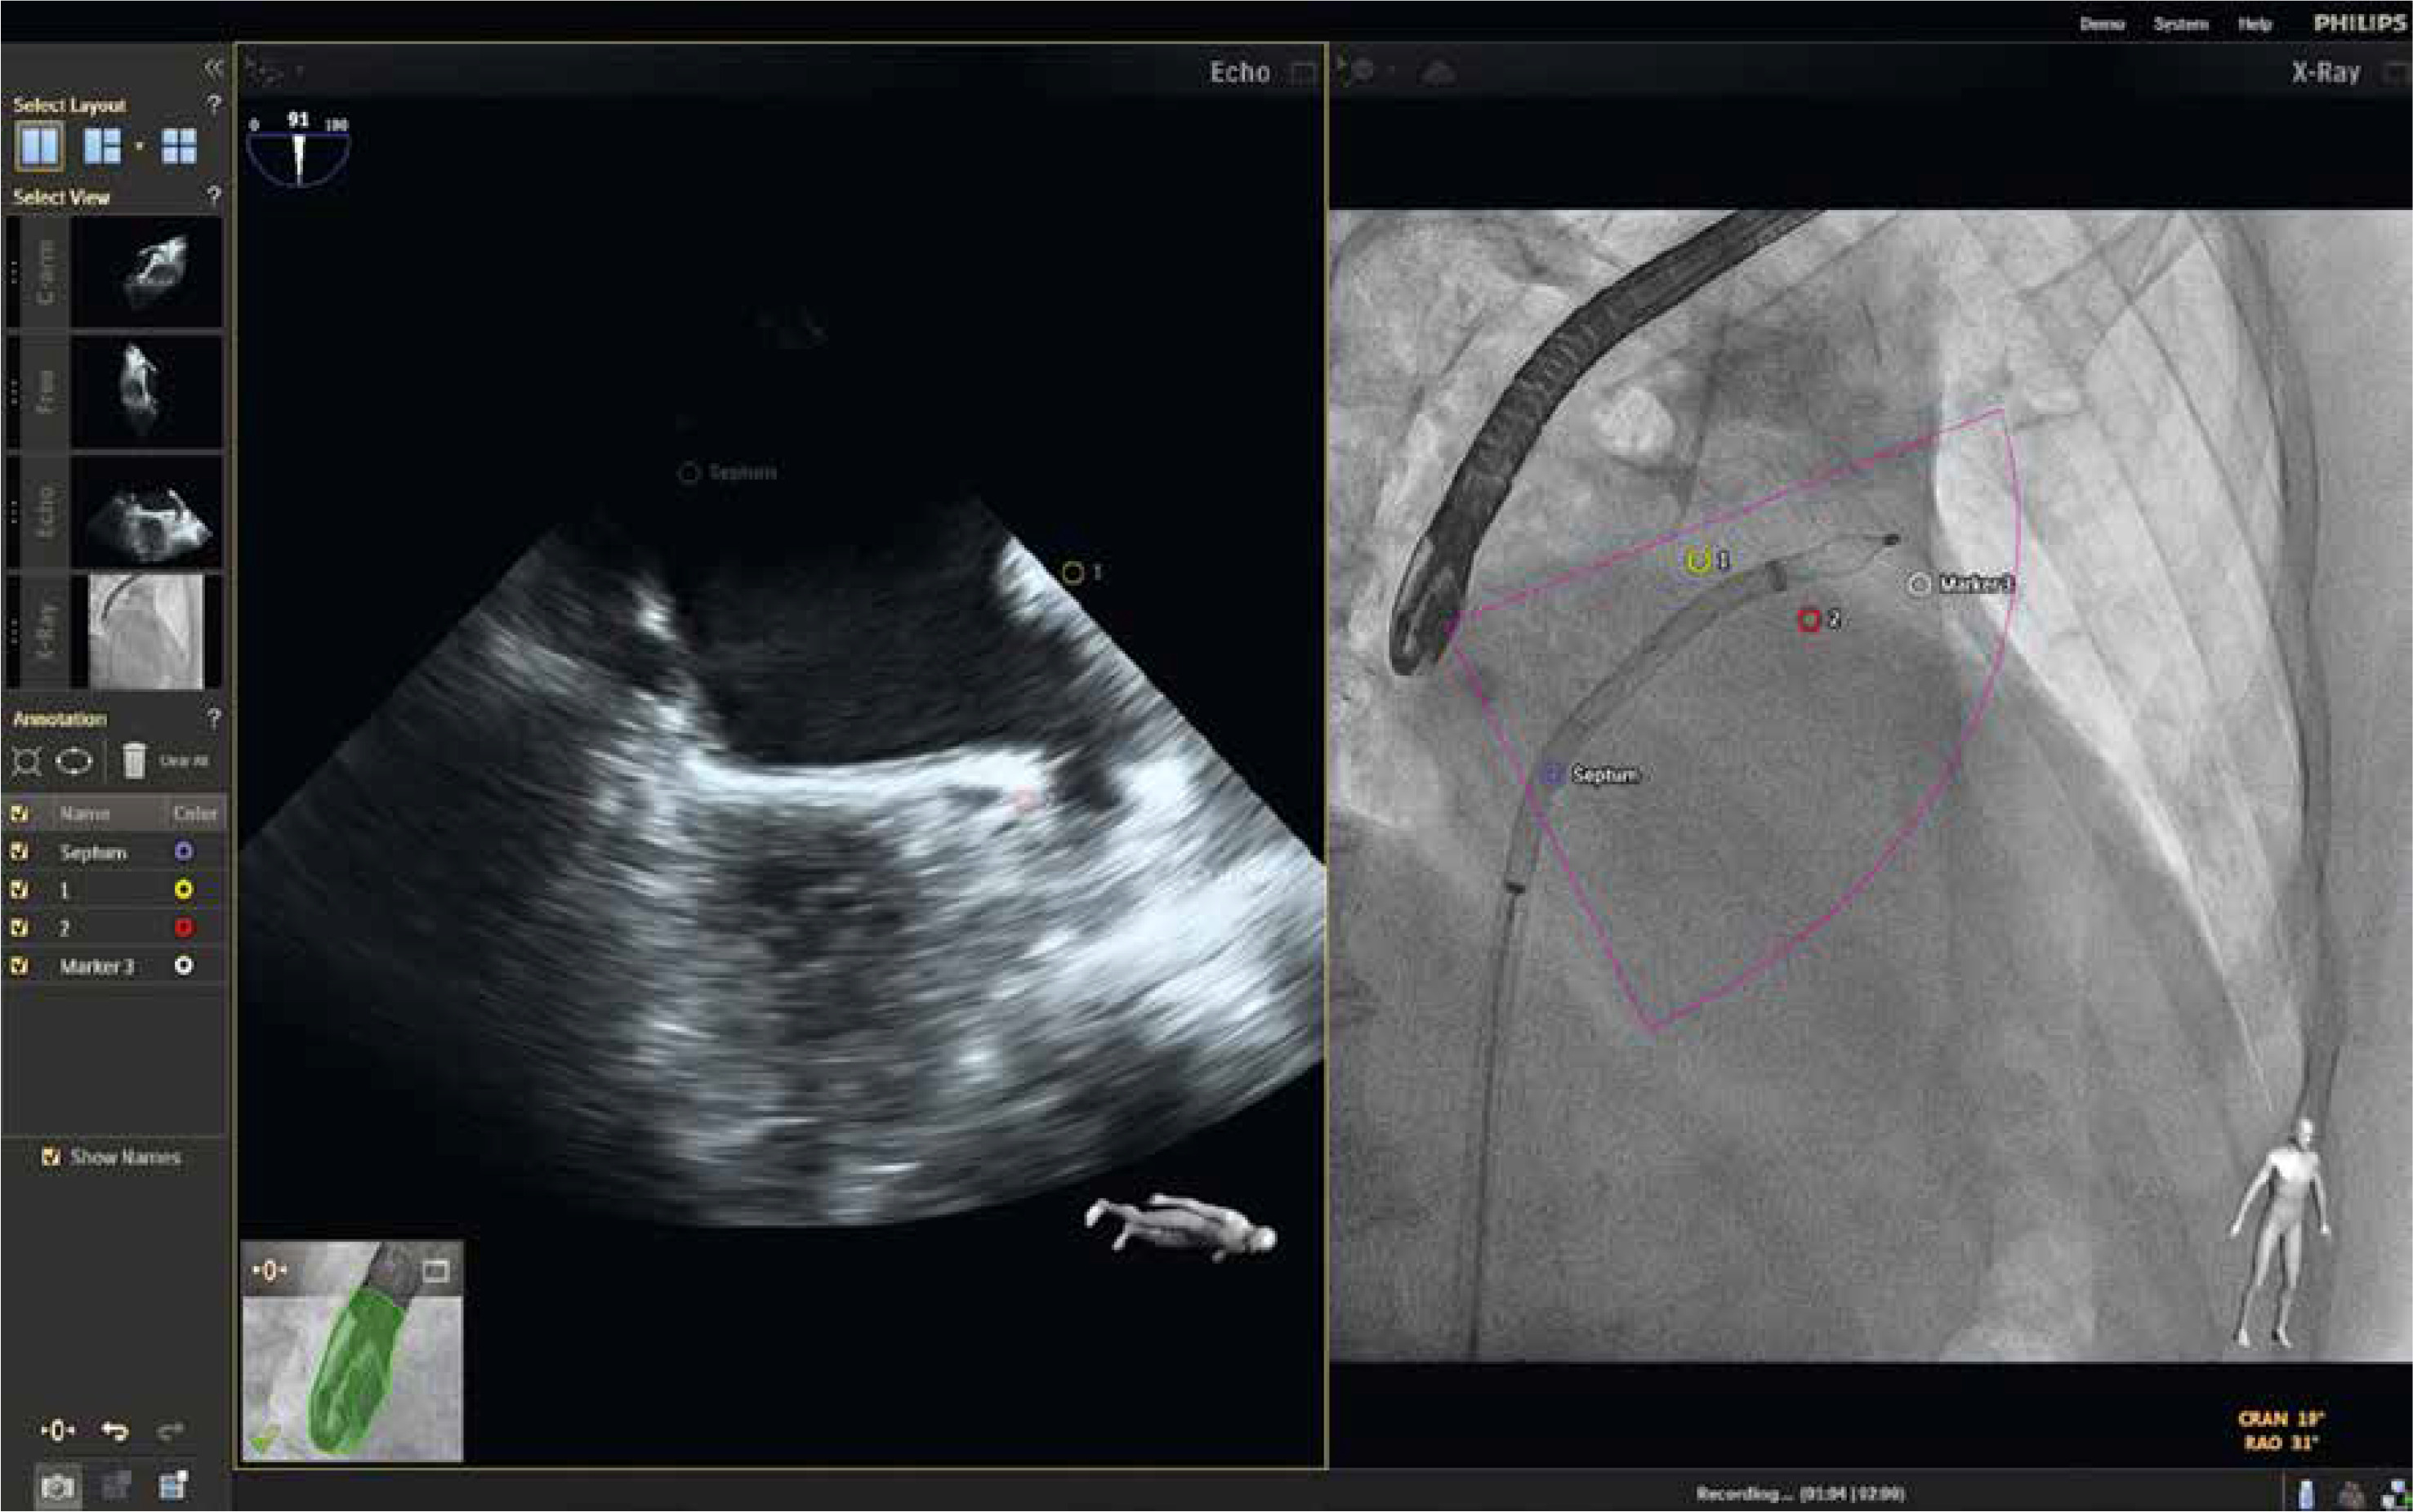

As described by Balzer et al., the EchoNavigator Release II (Philips, Best, Netherlands) system is a multimodal approach that synchronizes live echocardiography and fluoroscopy images in real time [6]. A calibration algorithm tracks the movement of the TEE probe using fluoroscopy. This is achieved through an image-based TEE probe localization algorithm and calibration procedure. After synchronization, the echocardiographic images from TEE automatically follow the motion of the fluoroscopic C-arm. The results of the coregistration process are displayed in a form that allows simultaneous visualization of an X-ray image and up to three echocardiographic views. The X-ray view shows the actual fluoroscopic image. The probe must be centered in this view to allow accurate coregistration of the probe TEE. If this is successful, the probe is displayed with a green outline; if not, e.g. after significant movement of the TEE probe, the probe is displayed with a red outline. The echo view shows images that can only be processed by the echocardiologist.

In the C-arm view, the beam path (i.e., the echocone) of the matrix array transducer is shown as a purple sector corresponding to the position of the TEE probe. Changes in the angulation, rotation, or position of the TEE probe are automatically displayed in this view. The free view displays 2D and 3D information that can be rotated, cropped, zoomed, or segmented by the operator using a sterile cover. Multiplanar reconstruction (MPR) software provides tools for 3D volume segmentation along the three axes (x, y, z) in real time or during post-processing, as well as quantitative analysis. Specific points of interest can be marked and are immediately displayed on the fluoroscopic image. These markers then serve as target points for guiding catheter manipulations. Intraoperative images of FI during LAAO are presented in Figures 1 and 2.